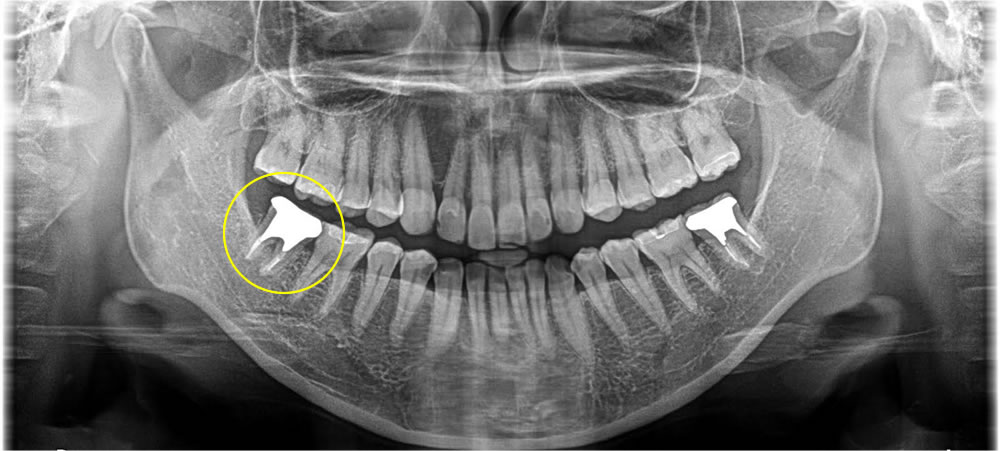

2次カリエスを治療後にセラミックインレーで修復した症例

年齢

20代

性別

女性